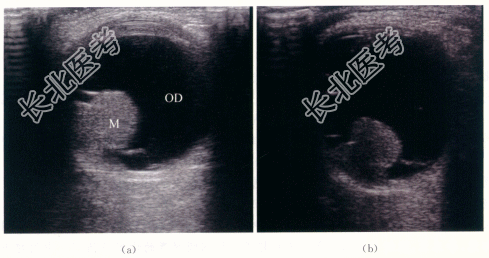

眼底检查示右眼玻璃体混浊。颞侧可见脉络膜实性隆起,呈棕褐色,表面有出血。隆起物周边视网膜呈青灰色隆起。

二、影像资料

- 简答题1、若患者诊断为脉络膜黑色素瘤,其声像图表现有哪些?